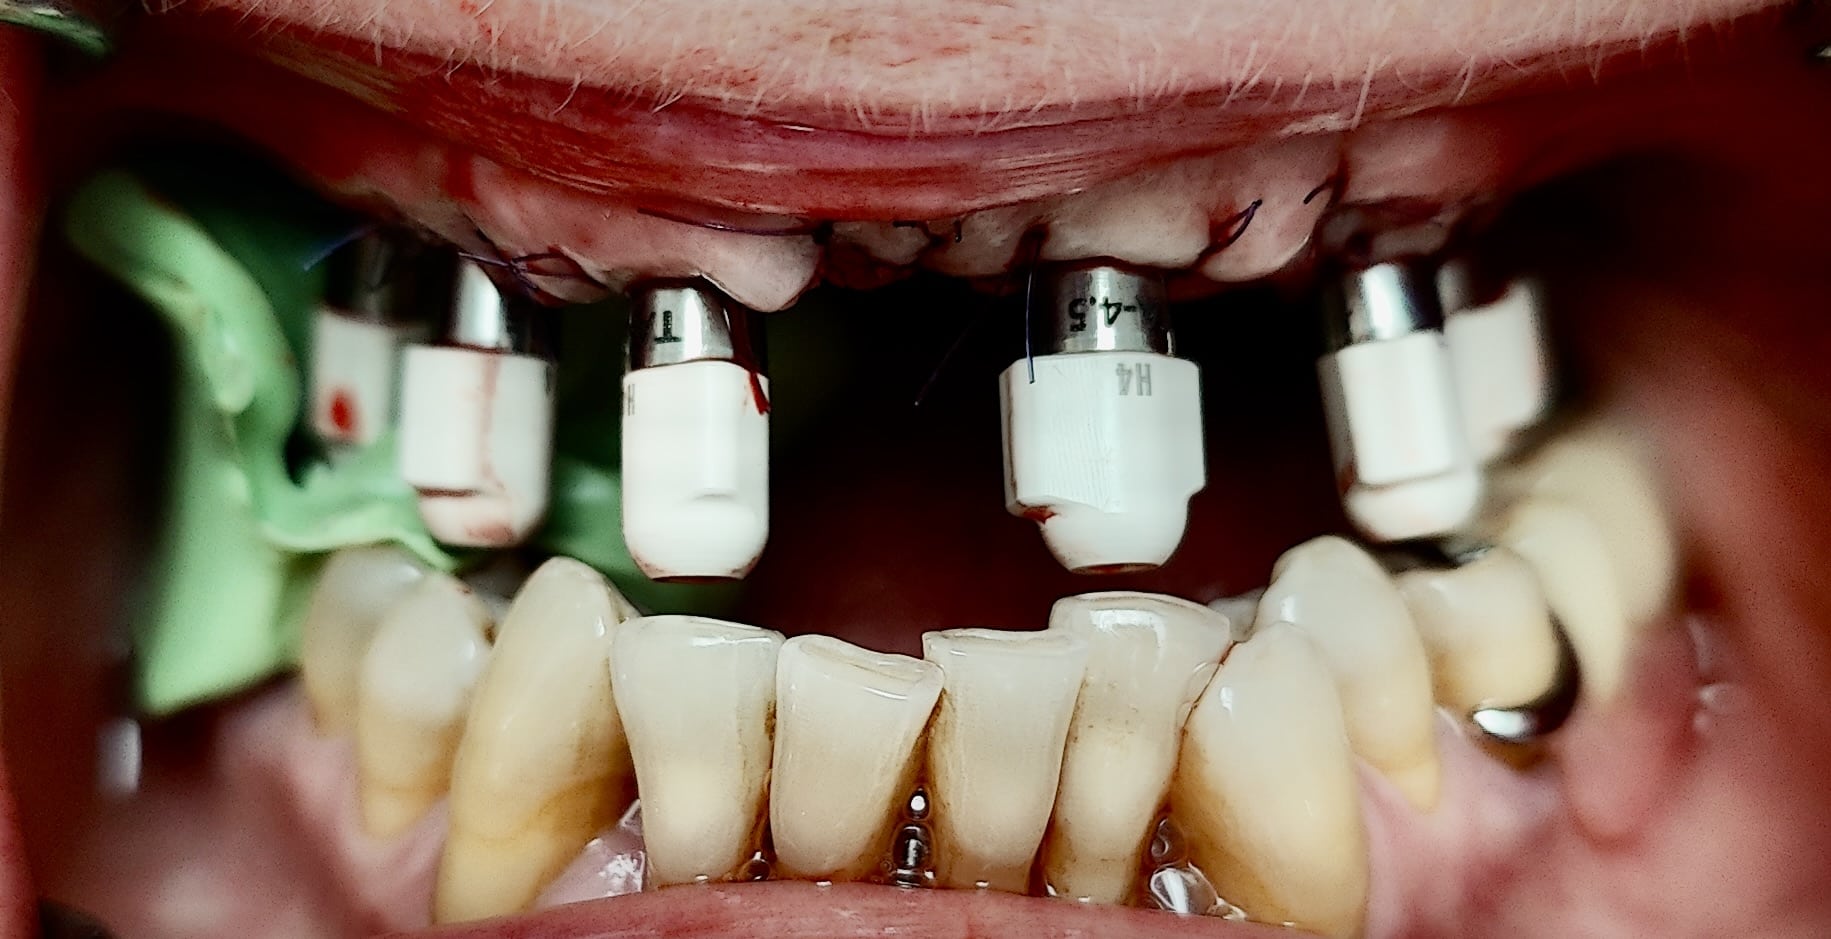

Vue clinique en fin de chirurgie des implants recouverts de piliers coniques :

Les piliers sont alors coiffés par des transferts pour enregistrement numérique (scanbodies) :